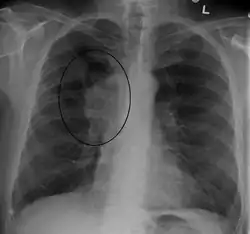

Diagnóstico

Principalmente clínico, a causa da obstrução deve ser investigada com punção aspirativa para biópsia linfonodal e mediastinal ou exames de imagem como raio X de tórax com contraste ou tomografia computadorizada. [4]